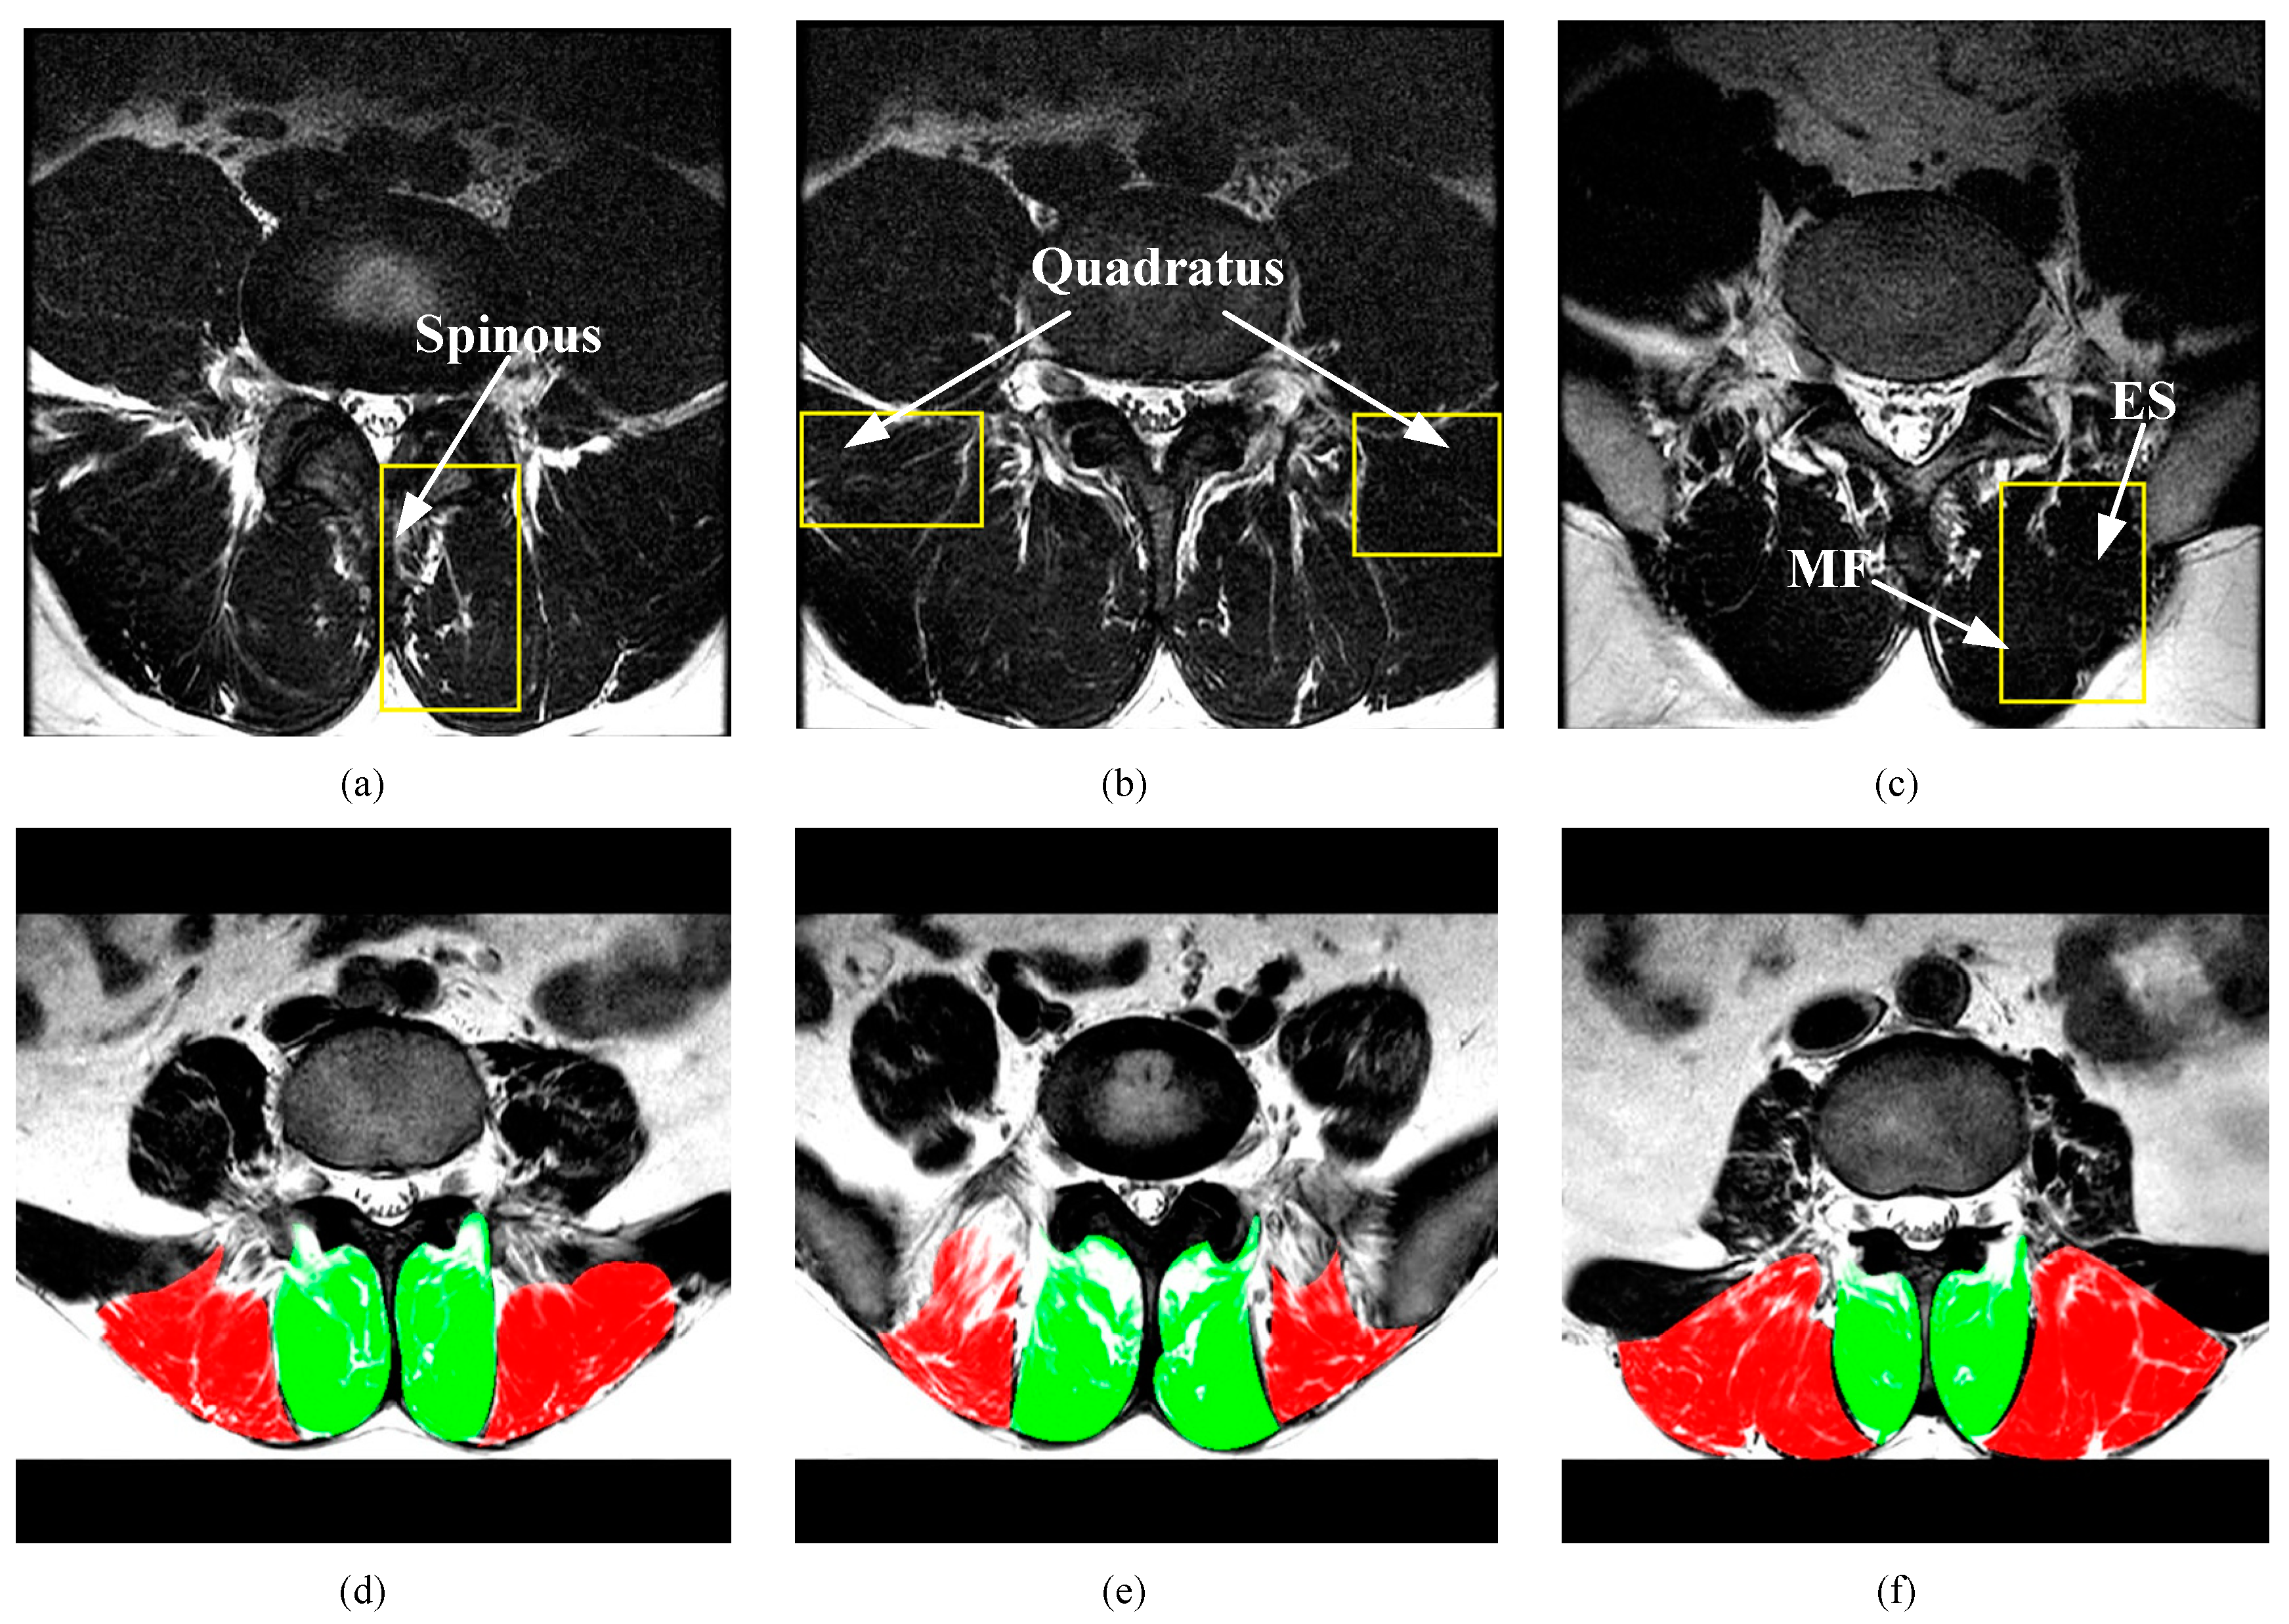

3.1. Dataset

3.4. Modules Analysis by Intra-Comparison